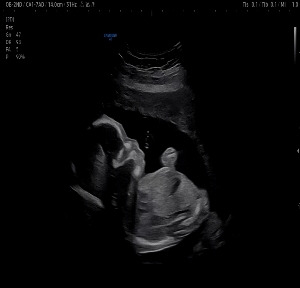

진료실에 들어서자 늘 그렇듯 의사 선생님은 조심스럽게 아내의 배 위에 초음파 기계를 댔다. 화면 속에는 이제 제법 사람의 형체를 갖춘 찹쌀이가 선명하게 비쳤다. 작은 팔다리가 바쁘게 움직이고, 몸을 뒤척이며 공간을 가득 채우듯 이리저리 돌아다녔다.

20주차 활발히 움직이는 찹쌀이